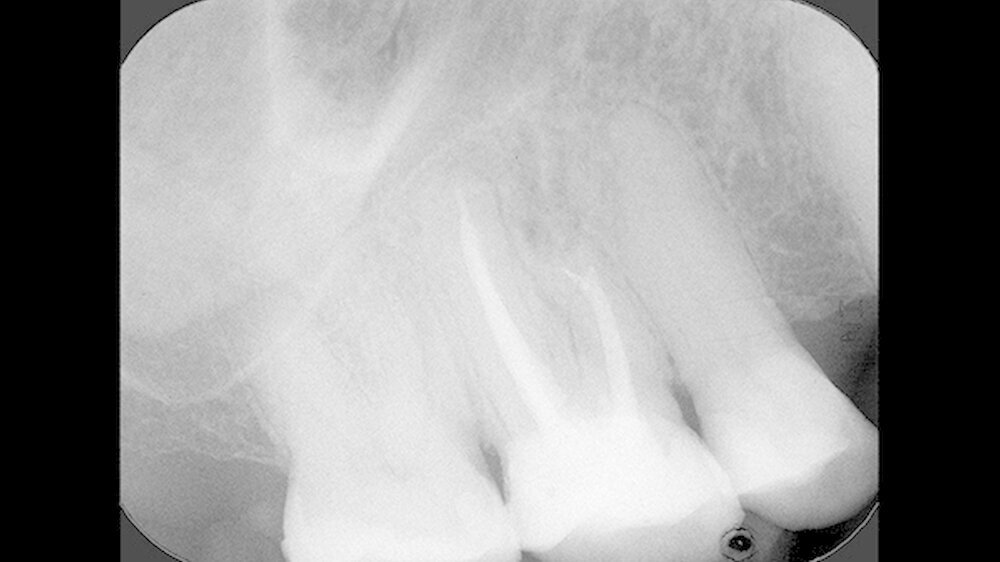

Mit einem ultraschallgetriebenen diamantierten, abgewinkelten Instrument wurden beide Wurzelkanäle der mesiobukkalen Wurzel von retrograd präpariert (Abbildung 3). Das frakturierte Instrument konnte so dargestellt (Abbildung 4) und entfernt werden.